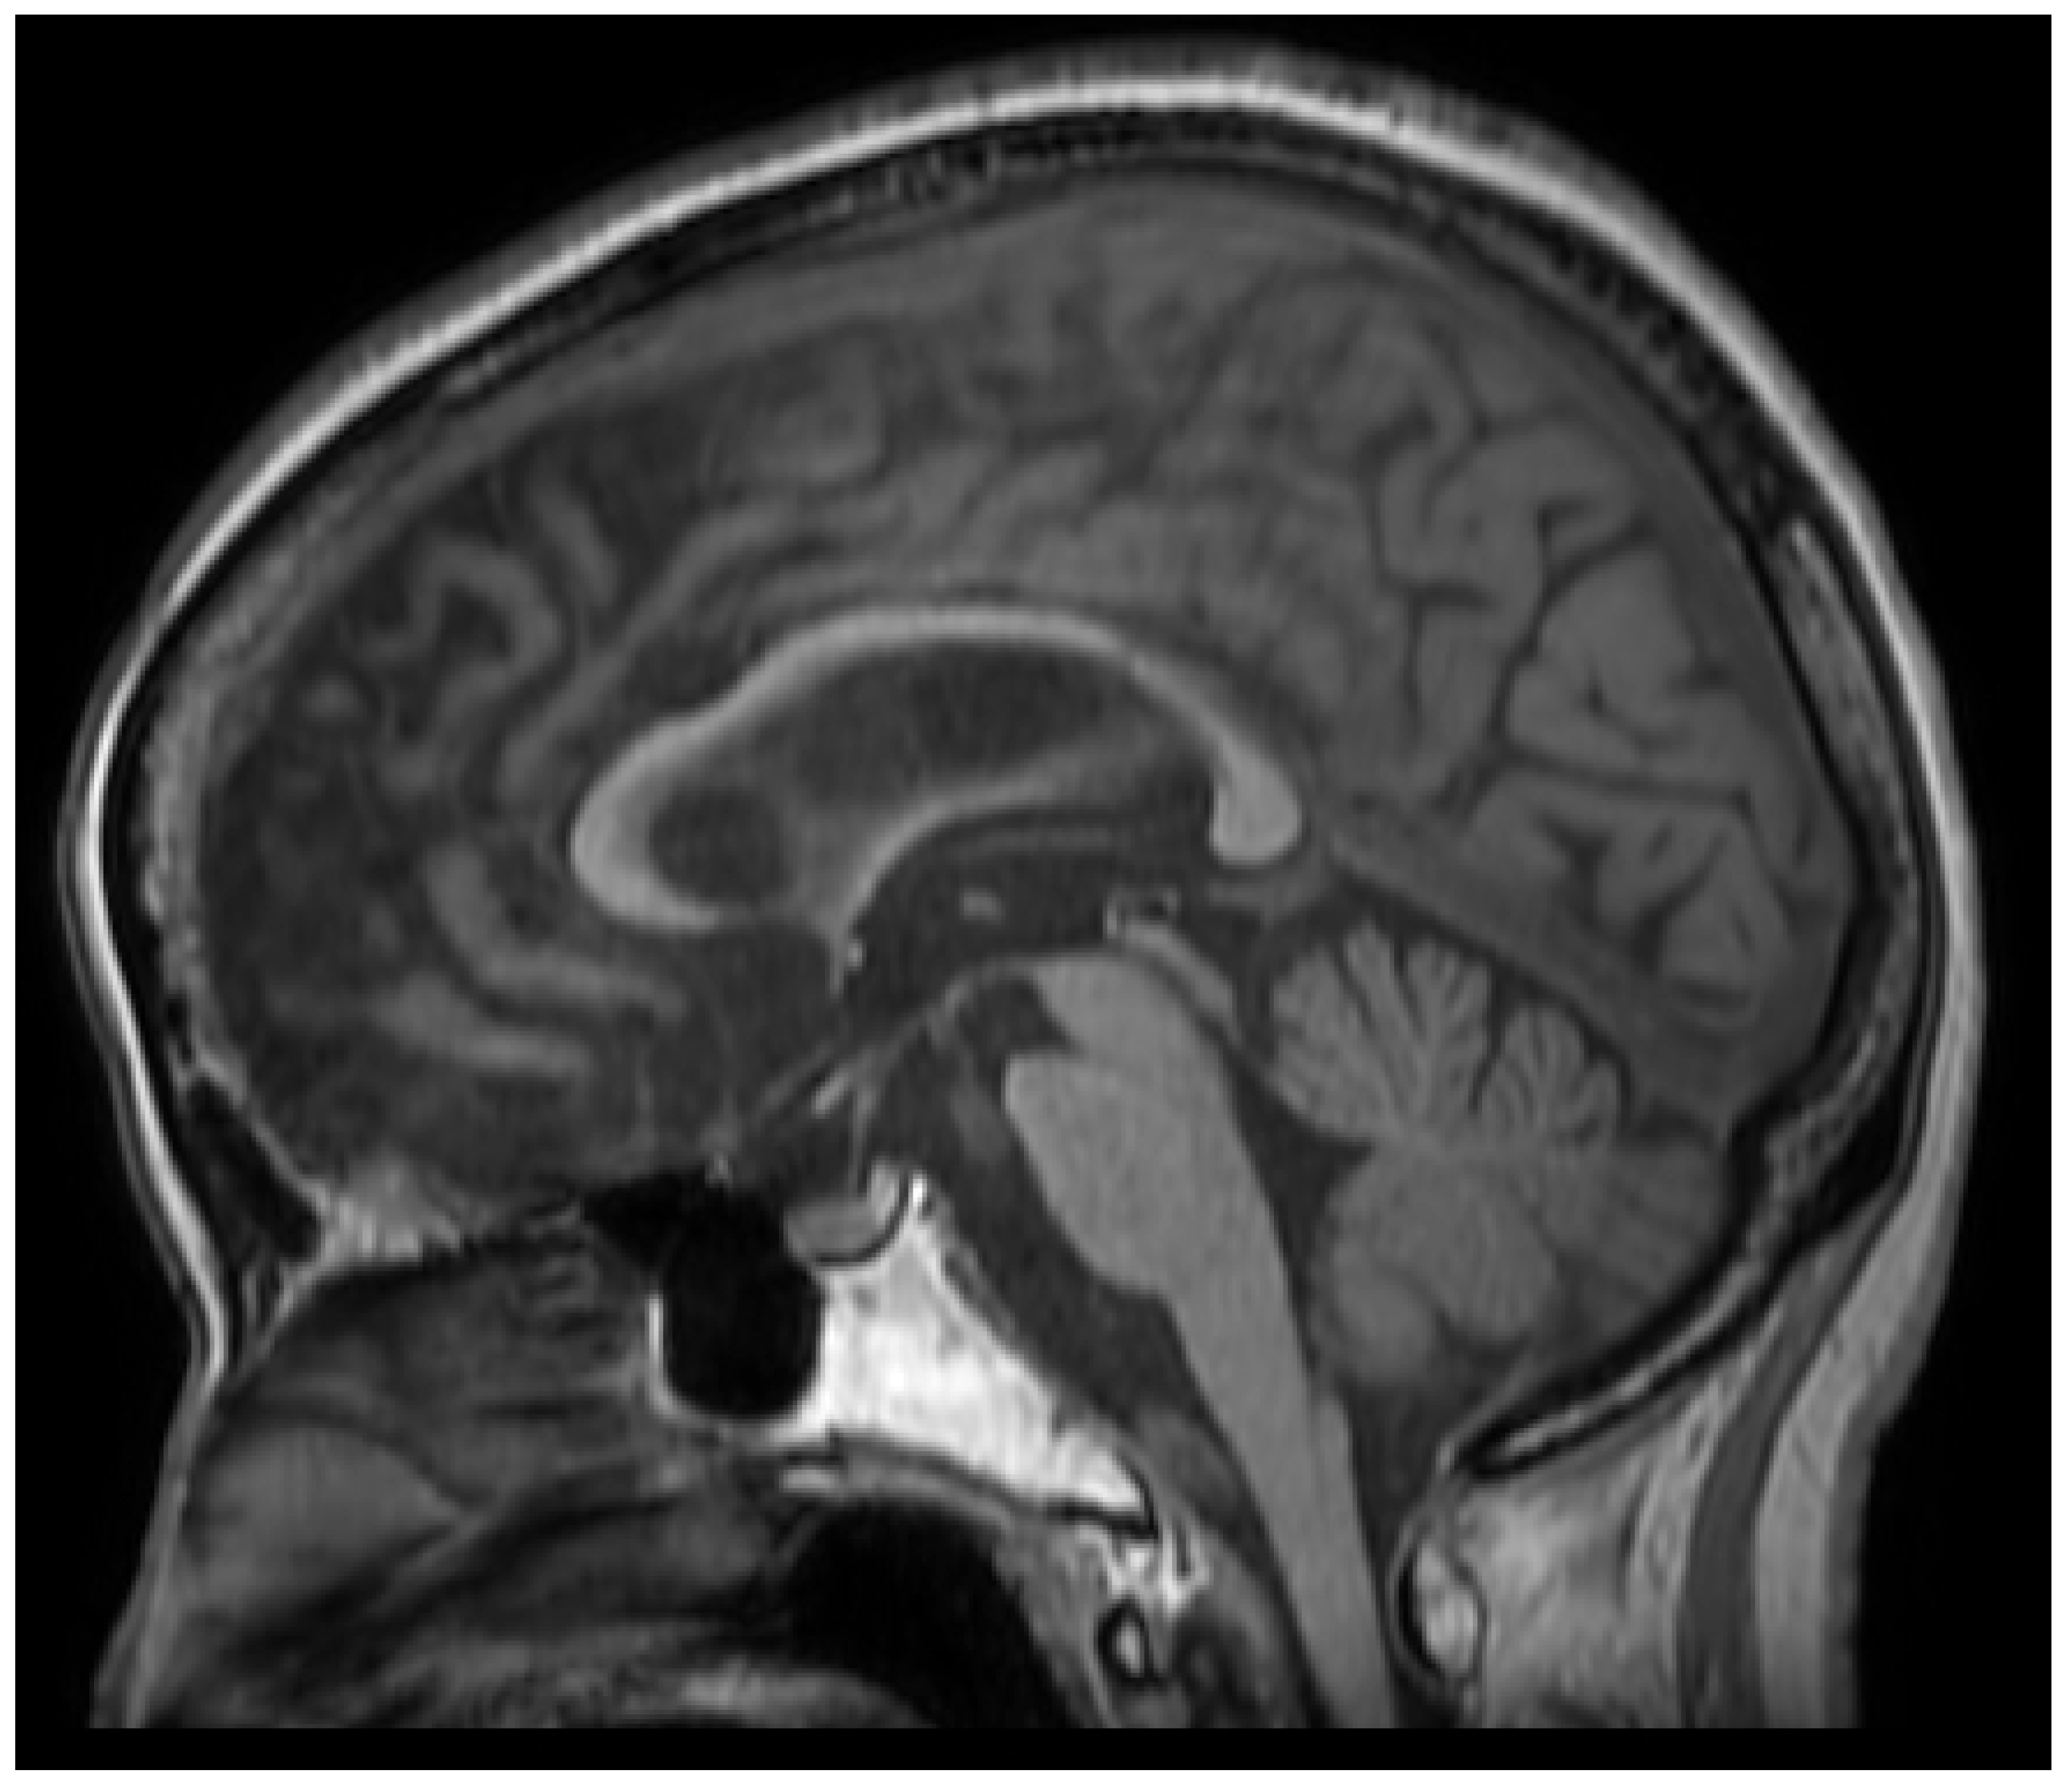

- da Rocha, A.J.; Oliveira, A.S.B.; Fonseca, R.B.; Maia, A.C.M., Jr.; Buainain, R.P.; Lederman, H.M. Detection of corticospinal tract compromise in amyotrophic lateral sclerosis with brain MR imaging: Relevance of the T1-weighted spin-echo magnetization transfer contrast sequence. AJNR Am. J. Neuroradiol. 2004, 25, 1509–1515. [Google Scholar] [PubMed]

- Carrara, G.; Carapelli, C.; Venturi, F.; Ferraris, M.M.; Lequio, L.; Chiò, A.; Calvo, A.; Sirgiovanni, S.; Cistaro, A.; Valentini, M.C. A distinct MR imaging phenotype in amyotrophic lateral sclerosis: Correlation between T1 magnetization transfer contrast hyperintensity along the corticospinal tract and diffusion tensor imaging analysis. AJNR Am. J. Neuroradiol. 2012, 33, 733–739. [Google Scholar] [CrossRef] [PubMed]